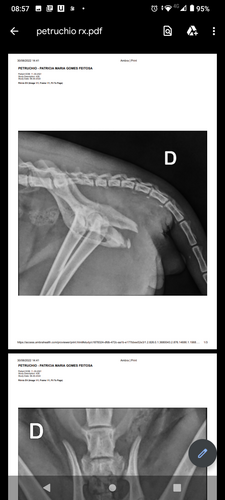

Olá pessoal estamos fazendo está vaquinha para ajudar o petruchio um gatinho de 7 meses que foi atropelado dia 29/06/22. O mesmo foi levado ao veterinário a clínica são Bernardo e lá deram os primeiros socorros,e precisou fazer raio-x a dona dele que é minha amiga/vizinha chamada Patrícia não tem condições tirou dinheiro do aluguel para pagar a consulta na clínica o raio-x ela consegui ajuda de uma moça! Mas ele vai precisar fazer cirurgia pois quebrou o fêmur estamos arrecadando dinheiro para fazer essa cirurgia nele! Quem quiser ir ver, ou fotos entrar em contato vou deixar o celular dela aqui 16 992854065 (Patrícia) e se quiser falar comigo este é o meu 16 992665825!